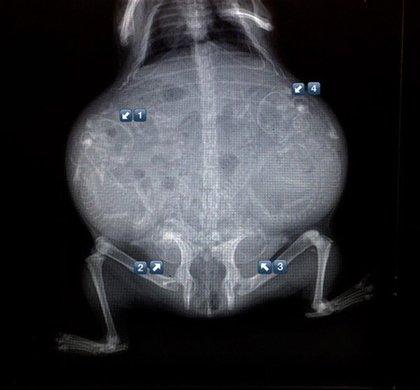

哈~這其實是動物懷孕的照片啦!美國《boredpanda》網站最近整理了一系列懷孕動物的X光照,從最常被人類飼養的貓、狗,乃至於蝙蝠、浣熊等都有,雖然小動物的誕生應該是可愛而溫馨,不過單看這些滿肚骨骸的X光照,還是覺得有點驚悚和詭異啊!

天竺鼠